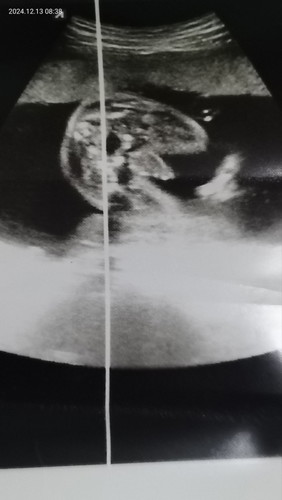

แบบนี้มีใครดูออกมั้ยค่ะ ถ่ายไว้ตั้งแต่ 18-20สัปดาห์แล้วคะ ตอนนี้ 30+6 ยังไม่ได้ซาวเพิ่มเติมเลย